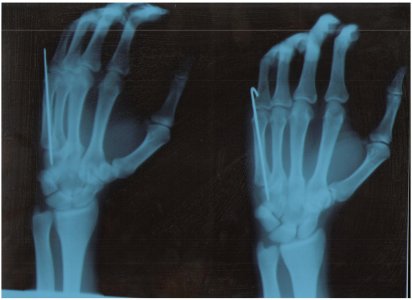

Через 3 недели после операции я сходил в травмпункт и сделал снимок кисти. На нем было видно что на месте перелома образовался небольшое пустое пространство (порядка 1-2 мм). Данным снимком, к сожалению, не располагаю. Травматолог сказал : место перелома заполнил хрящ и немного "раздвинул кости" - так и должно быть. Проблема в том, что после операции мне наложили лангет, который не фиксирует мизинец и безымянный палец. Пальцами, при желании, можно свободно двигать. Иногда в кисте, например когда зеваешь, происходят самопроизвольные сжатия пальцами в кулак. Может ли то, что гипс не фиксирует полностью кисть и травмированным пальцем можно шевелить повлиять на сростание кости. Через неделю мне делать контрольный снимок и хотелось бы провести новый год без гипса. Сегодня так же получил глухой удар по спице в направлении к локтю и сейчас кисть немного болит.